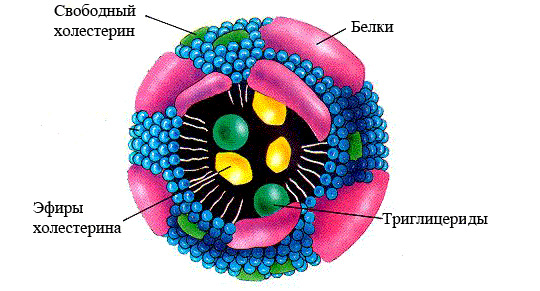

- Липопротеины — основная форма транспортировки липидов в организме. Поскольку липиды не растворимы в воде, они не могут выполнять свои функции самостоятельно. В крови липиды связываются с белками, называемыми апопротеинами, что делает их растворимыми и образует новое соединение — липопротеид или липопротеин. Эти термины взаимозаменяемы и часто сокращаются до ЛП.

Липопротеины играют ключевую роль в транспортировке и обмене липидов. Хиломикроны переносят жиры, поступающие с пищей, ЛПОНП обеспечивают доставку эндогенных триглицеридов к местам утилизации, ЛПНП способствуют поступлению холестерина в клетки, а ЛПВП защищают от атеросклероза.